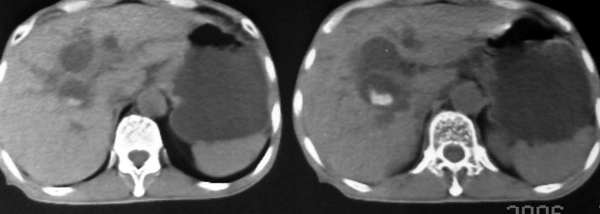

以下是引用lkc8963在2006-1-19 21:13:00的发言:[br]右半结肠及盆腔小肠明显积液扩张,腹腔内无明显渗出;右半结肠近端见多发点状高密度影;胆管内多发结石。[br]不知临床有哪些资料。本例需考虑胆石性肠梗阻的可能性,或胆系结石漏至结肠(异常通道如瘘)。

以下是引用wawaquan在2006-1-19 23:55:00的发言:[br]胆系结石,右半结肠梗阻:考虑横结肠占位(横结肠壁厚呈肿块状)。